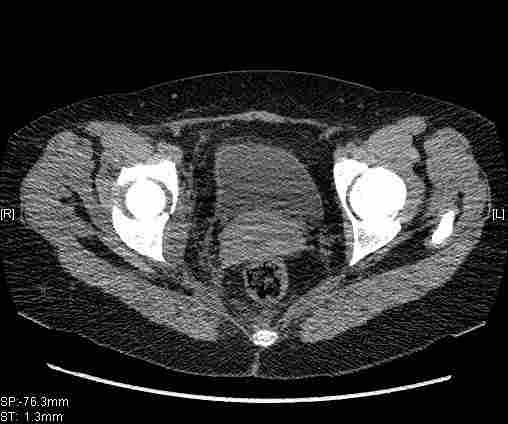

Женщина,58 лет, после ДТП 6 суток. Первично повреждение расценено как переломы ветвей лонной кости. После подтверждения повреждения вертлужной впадины,как чаще всего случается, вопрос встал о тактике. БОльшинство за консерватиное лечение.К сожалению кт у нас "во время" сломался. Прилагаю стандартные снимки вертлужки. У меня следующие вопросы к коллегам:1. Правильно ли рассценивать это повреждение как Т-образный перелом вертлужнй впадины?2. Можно ли добиться анатомической репозиции поверхности вертлужной впадины скелетным вытяжением в данном случае, если нет, что будет этому препятствовать?3. Если смещение останется таким как сейчас, через какое время появится необходимость эндопротезирования (по вашему опыту)?Спасибо.

Удалось сегодня вывести пациентку в соседнюю больницу, где есть кт. Срезы сделаны только горизонтальные.

|

Приветствую,Антон.Рункова рядом нет,но после полученных данных КТ,обсуждали совместно.Итог обсуждения-развернутый ответ дать не получится,т.к.срезы выбраны не информативные.Если ориентироваться на данные 3D,то ,ИМХО,можно лечить на вытяжении.